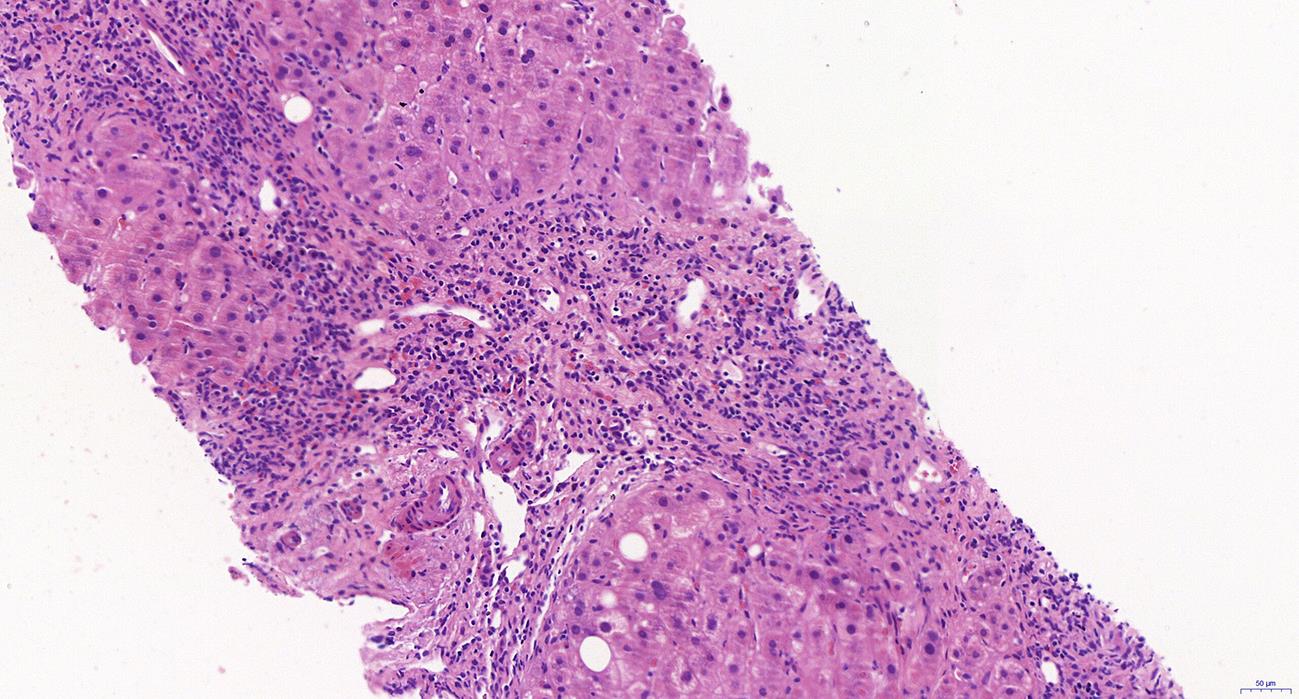

Autoimmune pancreatitis (AIP) is a rare disease, and its diagnosis should be made based on a comprehensive evaluation of clinical, radiological, serological, and pathological findings. At present, AIP is classified into two subtypes of type 1 (identified as the pancreatic manifestation of IgG4-related disease) and type 2 (identified as the pancreas-specific disorder independent of IgG4). Although type 1 and type 2 AIP seem to have different pathogeneses, they tend to have similar radiological findings and exhibit a good response to corticosteroid therapy. This article mainly reviews the histopathological features of the two subtypes of AIP, especially the diagnostic challenges encountered in the interpretation of specimens obtained through endoscopic ultrasound-guided fine needle aspiration/biopsy, to as to help pathologists enhance the accuracy of the diagnosis of AIP.